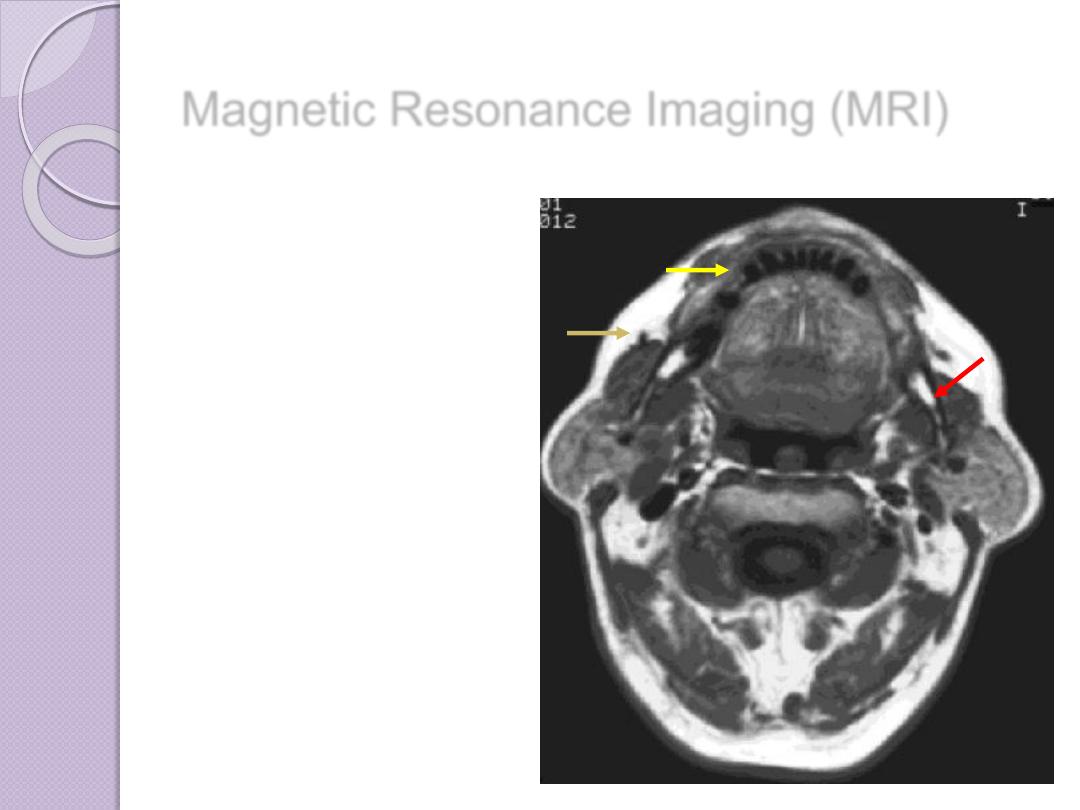

Magnetic Resonance Imaging (MRI)

Magnetic Resonance Imaging (MRI)

Magnetic Resonance Imaging (MRI)

At the atomic level, water and adipose are

composed of hydrogen, oxygen, carbon, and

phosphorus atoms. The

hydrogen atom

contains a proton and an orbiting electron.

A spinning charged particle (the proton) produces a local

magnetic field